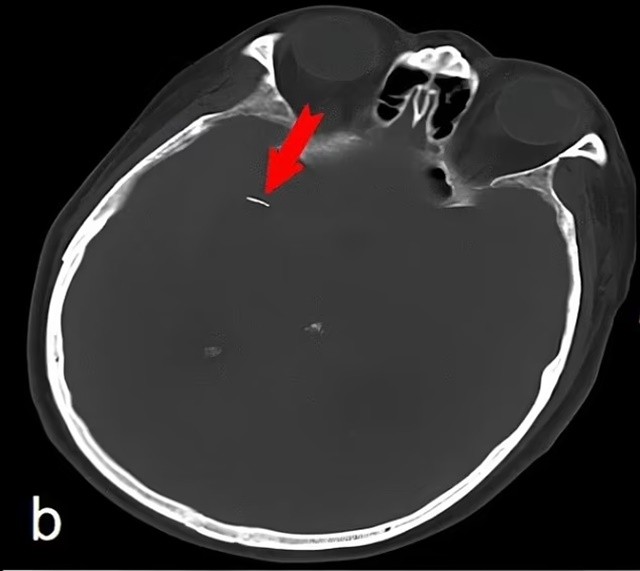

Mới đây, trường hợp 1 bệnh nhân tưởng mình bị chứng phình động mạch đã đến bệnh viện khám và được phát hiện có kim châm cứu cắm vào trong não gây xôn xao. Kết quả quét cho thấy chiếc kim dài 0,5 inch (gần 1,3cm) 'màu vàng' và 'hơi nhọn' nằm trong động mạch bên trong não của người đàn ông 74 tuổi. Nó gây ra chảy máu trong khiến người đàn ông này gặp vấn đề về trí nhớ.

Trước đó, chiếc kim nhỏ xíu bên trong cơ thể người đàn ông được tìm thấy trong một động mạch chạy qua não phía sau mắt phải - được gọi là động mạch não giữa bên phải. Có ý kiến cho rằng chiếc kim có thể đã bị gãy trong quá trình điều trị châm cứu và sau đó được đưa vào động mạch phía sau mắt.

Hiện chưa rõ nguyên nhân dẫn đến vết vỡ nhưng điều này có thể liên quan đến một cú ngã, va đập mạnh vào đầu hoặc do vị trí của kim trong hộp sọ bị dịch chuyển. Người đàn ông đã được đưa đến bác sĩ một giờ sau khi vấn đề về trí nhớ của anh ta xuất hiện, ban đầu gia đình lo ngại anh ta đang bị chứng phình động mạch. Nhưng kết quả quét cho thấy cây kim đâm vào não anh ấy đang chảy máu.